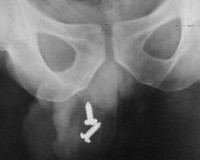

В большинстве случаев диагностика инородного тела кишечника не вызывает затруднений. Важная роль принадлежит оценке жалоб пациента и анамнеза. Осмотр абдоминального хирурга позволяет предварительно оценить прогноз и определить тактику лечения, составить план обследования пациента. В лабораторных анализах при отсутствии осложнений изменений нет, возможен лейкоцитоз. Обзорная рентгенография брюшной полости дает возможность визуализировать инородное тело, оценить его размеры и расположение.

При инородных телах малых размеров, а также неконтрастирующихся при рентгенографии (например, из дерева, алюминия, пластмассы), проводится рентгеноскопия с введением контрастного вещества. Данный метод обследования позволяет не только обнаружить предмет, но и оценить проходимость кишечника. Для выявления предметов в толстой кишке применяется колоноскопия, при локализации в прямой кишке – пальцевое ректальное исследование, при его недостаточной информативности, подозрении на повреждение кишечника проводится ректороманоскопия.